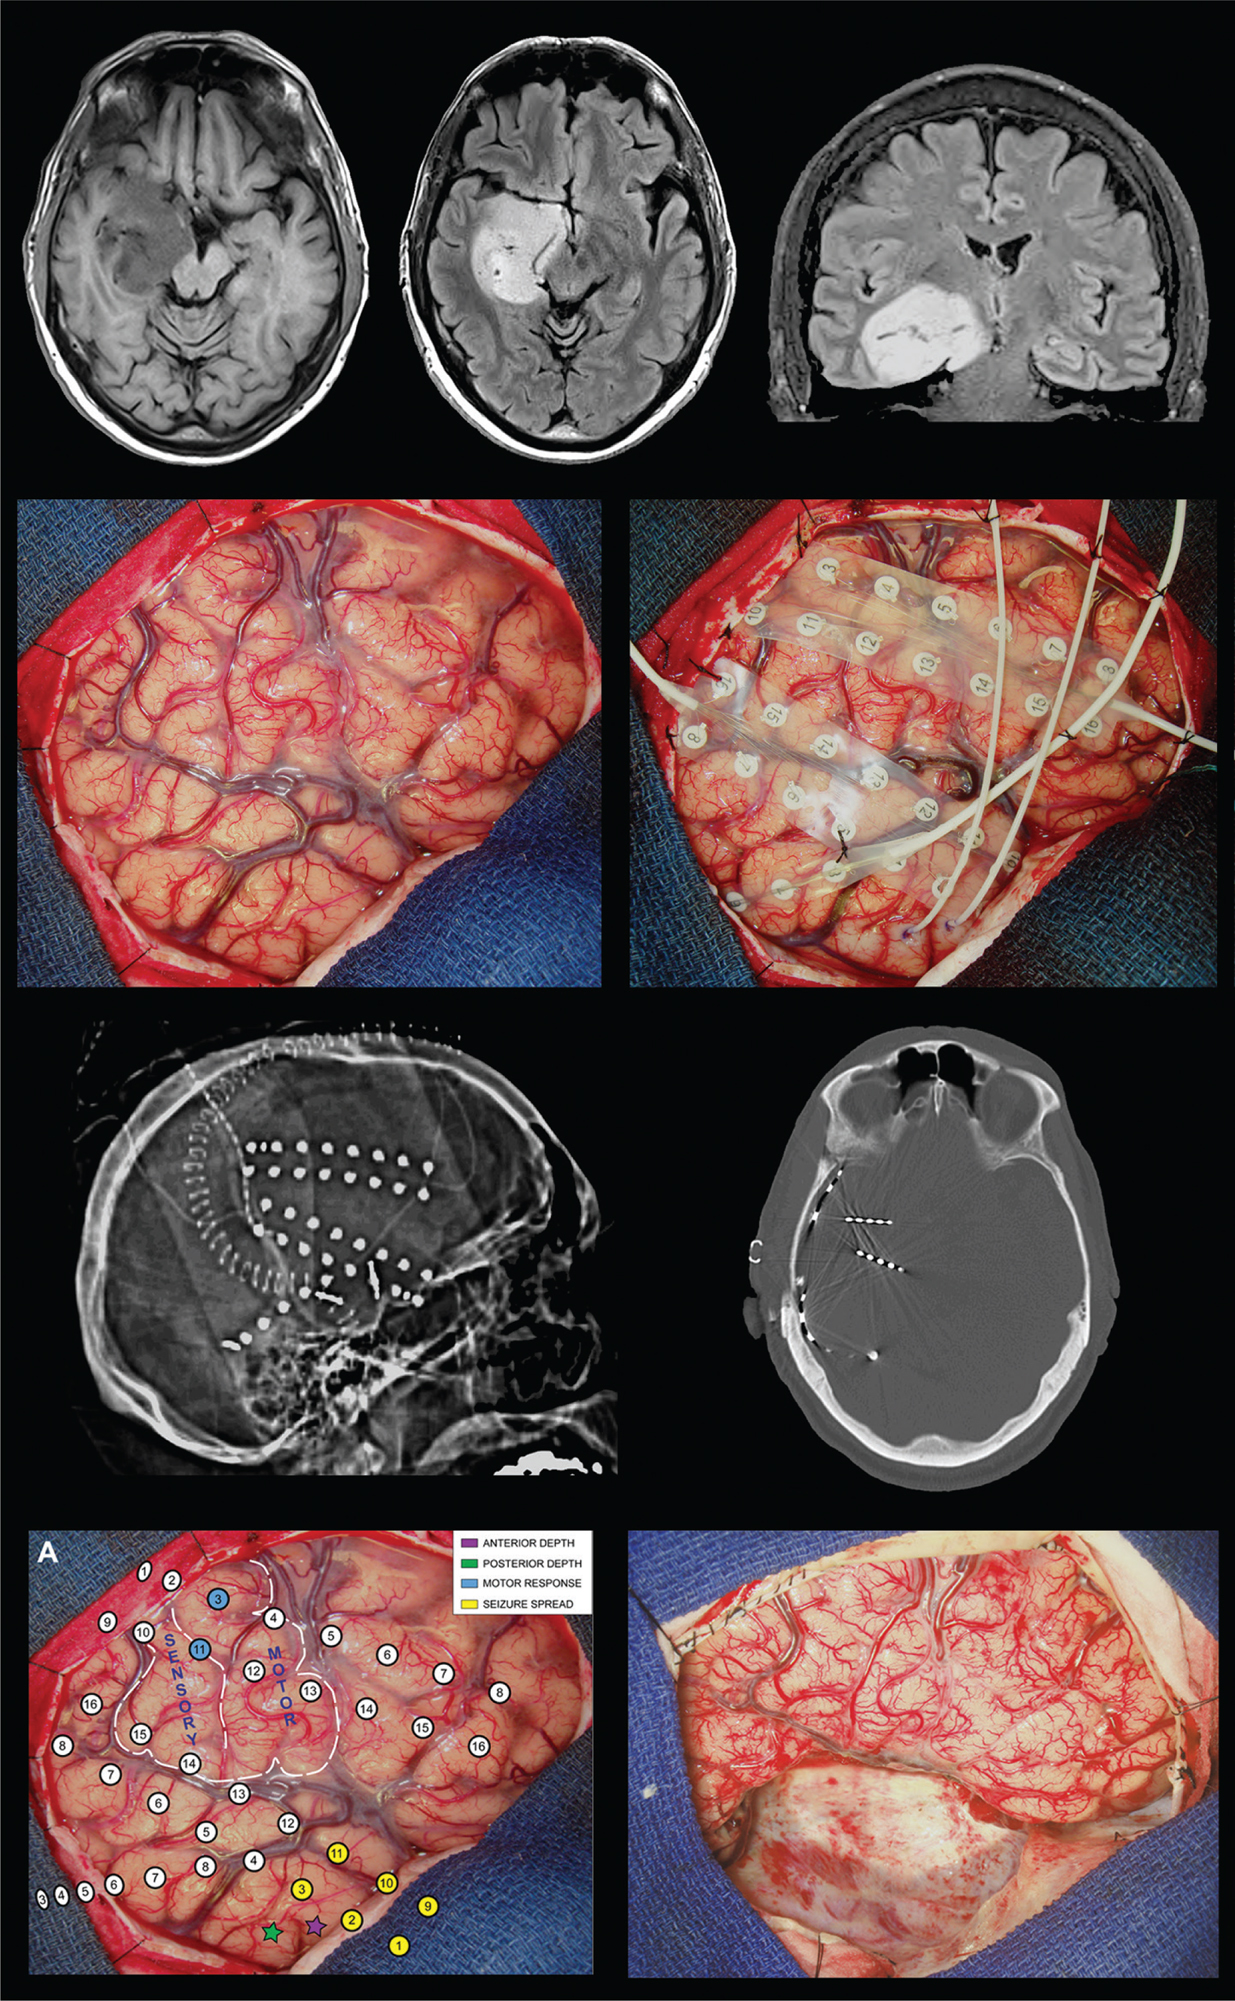

Different surgical treatment options as well as advanced imaging modalities are available for patients with BTRE. Intraoperative cortical brain mapping with electrocorticography, radiosurgery, and laser interstitial thermal therapy are additional surgical techniques that can be effectively utilized in BTRE. EEG mapping is also another modality that can be beneficial for identifying the epileptogenic focus. Epileptogenic foci can be identified within or overlying the tumor, the peritumoral tissue, and even distant areas away from the tumor (Figure 2) (61, 62). The extent of tumor resected directly correlates with seizure freedom; however, patients may benefit from subtotal resection if the epileptic focus was identified before the resection, especially if the tumor is in eloquent areas of the brain (62). It is essential to identify patients where the tumor is not the primary epileptogenic focus, as they may benefit from a combined approach encompassing both tumor resection and epilepsy surgery (61).

Fig 2

Figure 2. Surgical management of brain tumor-related epilepsy. This patient presented with recurrent seizures and a non-enhancing mass in the right medial temporal region (top row). Intraoperative photographs during intracranial electrode implantation (second row). Postsurgical CT scan showing placement of subdural grid electrodes and depth electrodes (third row). Intraoperative photographs showing intracranial electrode arrays with cortical mapping results and following resection of the tumor and epileptogenic tissue (bottom row).